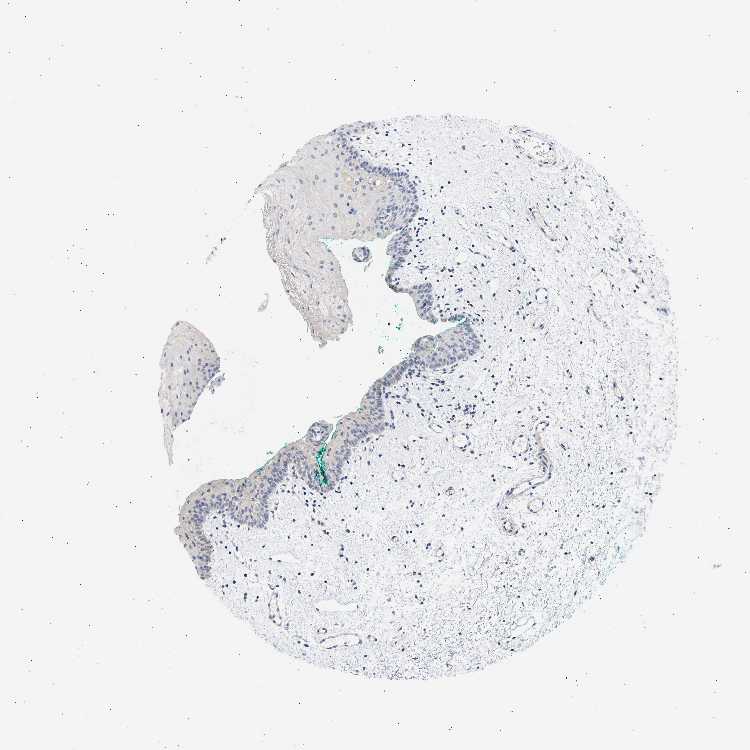

TISSUE PRIMARY DATA ORAL MUCOSA Show tissue menu

ORAL MUCOSA - Antibody stainingi

Antibody staining in the annotated cell types in the current human tissue is reported as not detected, low, medium, or high, based on conventional immunohistochemistry profiling in selected tissues. This score is based on the combination of the staining intensity and fraction of stained cells.

Each image is clickable and will lead to virtual microscopy that enables deeper exploration of all samples and also displays staining intensity scores, fraction scores and subcellular localization as well as patient and tissue information for each sample.

Antibody HPA014447Antibody HPA048045

Squamous epithelial cells Not detectedNot detected